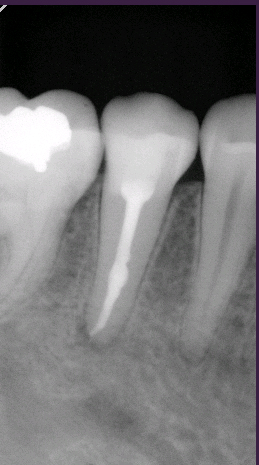

- Endodoncie

- Jedná se o jeden z nejsložitějších výkonů konzervační stomatologie. Životnost zubu je zcela ovlivněna technikou a kvalitou provedení daného ošetření. Proto v našich ordinacích používáme nejmodernější postupy ošetření kořenových kanálků. Standardní metody jsou zcela obsoletní a proto je svým pacientům nedoporučujeme, jelikož nelze zaručit dlouhodobě dobrou prognózu takto ošetřeného zubu.

Nadstandardní postup obsahuje:

Stanovení délky kořenového kanálku apexlokátorem Raypex 5 nebo RVG. Opracování kořenových kanálků systémem MTWO (přístrojem VDW Endo IT Professional) nebo systémem Reciproc (ošetření kanálků pouze jedním nástrojem). Plnění kořenových kanálků nadstandardními metodami, např. laterální kondenzace. - Protetika